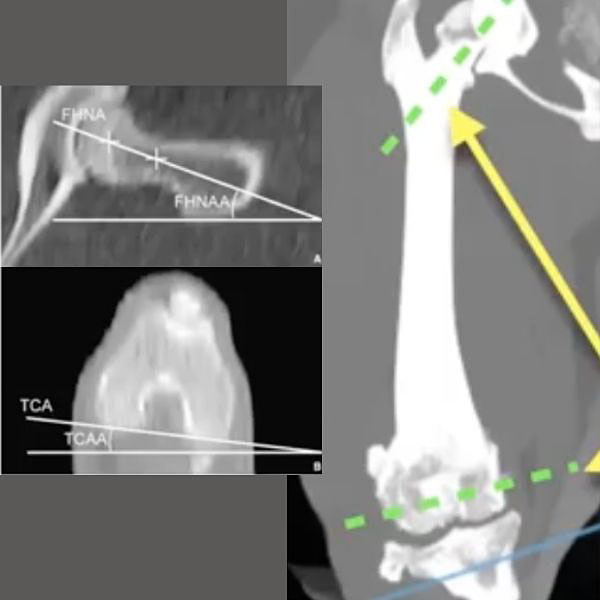

For the femur, the amount of torsion between the head and neck of the proximal femur and the condyles of the distal femur is called the femoral anteversion angle (FAA) and ranges between 16–31°. In Fig 10 (12:53), on the right is an axial plane view of the distal femur showing the condyle, and on the left an axial plane view of the proximal femur along the angle of inclination. The methodology for this has been previously published so we won’t go into detail in this article. Again, the Atlas of Clinical Goniometry and Radiographic Measurement of the Canine Pelvic Limb by Massimo Petazzoni and Gayle H Jaeger is an excellent reference source.

Anteversion is when the femoral head and neck points cranial to the frontal plane of the femur, and retroversion is when it points caudal to the frontal plane of the femur. Normoversion is when the femoral head and neck are at right angles to the sagittal plane. Anteversion has a positive angle and retroversion has a negative angle.

Why is this important? When we take a well-positioned, true lateral radiograph, you can get a visual impression of the anteversion angle. (Fig 11, 13:43) The image on the left is at the top end of normal, and as a rule of thumb, in a perfectly positioned lateral x-ray of the femur (whereby the femoral condyles are overlapping) about 50% of the femoral head would be cranial to the dotted yellow line that marks the cranial edge of the femur. On the right image there is no femoral head visible as it is obscured by the greater trochanter. The condyles in this image are superimposed so this confirms that the X-ray or in this case CT rendering is a true lateral. This apparent absence of any of the femoral head cranial to the line that marks the cranial edge of the femur in a well-positioned lateral radiograph, gives a strong indication that the femoral head and neck have a decreased angle of anteversion or are relatively retroverted. A decreased angle of anteversion or relative or absolute retroversion is associated with medial patella luxation as in the standing dog this externally torses or supinates the femoral condyles and trochlea groove away from the sagittal plane. This can create quite significant frontal plane offset and is strongly associated with MPL.

This concept of how a reduced angle of anteversion or relative retroversion of the femoral head and neck in the proximal femur creates external torsion of the distal femur and femoral condyles can be difficult to understand initially. The best way to understand this is to recognize that a normal acetabulum is retroverted by typically 15–25 (Fig 12, 14:51). If you think of the femoral head and neck “docking” into this retroverted or slightly caudally facing acetabulum, that means the femoral head and neck should have a corresponding cranially facing angle of anteversion.

So when we think of a decreased angle of anteversion / relative retroversion, we need to think of the femoral head and neck as being “docked” or relatively fixed with respect to its angulation into the acetabulum and so consider what's happening distally with the femoral condyles and trochlea groove. In Fig 13 (15.28), we’re creating retroversion, and you can see that with a fixed femoral head and neck, it externally torses or supinates the trochlear groove. So, a decreased angle of anteversion / relative retroversion creates this classic supination or external torsion of the trochlea groove. The lower the angle of anteversion / the more relatively retroverted the femoral head and neck are, the greater the frontal plane offset you will palpate between the center of the trochlea groove and the tibial tuberosity. Unsurprisingly the higher grades of severity of MPL are associated with correspondingly decreased magnitude of FAA (relative or absolute retroversion).

The generally accepted method is to measure the offset between the caudal tibial condylar axis proximally and the cranial tibial axis distally to determine the magnitude of tibial torsion (Fig 15, 16:26). A normal distal tibia is internally torsed or pronated approximately five degrees relative to the proximal tibia. Supination or external torsion of the distal tibia creates corresponding abnormal pronation or internal rotation of the tibial tuberosity as expedience of ambulation has the toes and pes pointing roughly sagittal in the direction of movement.